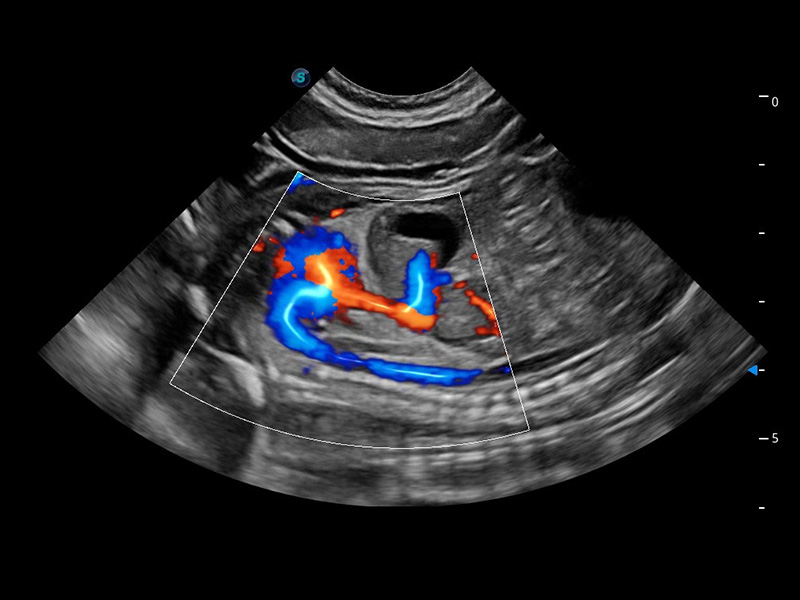

(犬)四腔心血流